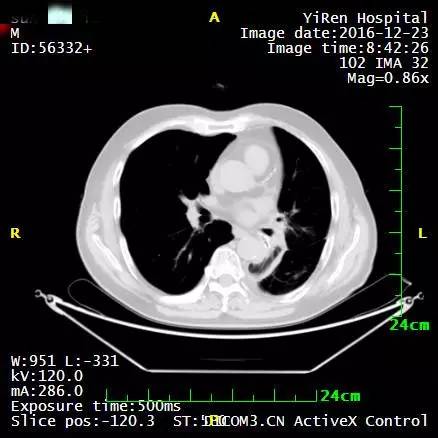

2016年3月,王先生因咳嗽加重就诊于当地医院,支气管镜病理检查提示:考虑小细胞癌的可能性大。

化疗一周期,病情无改善症状加重。

2016年4月,王先生接受了A45治疗,一个月后复查,病灶明显缩小,2016年7月复查,病灶进一步缩小,由于A45治疗具有明显的远观效应,能够激发自身的免疫系统,长期有效的消灭体内肿瘤,2016年12月,王先生肺部病灶几乎全部消失。

治疗前

治疗后

治疗后两个月

治疗后7个月

目前王先生状态良好,没有任何复发迹象。